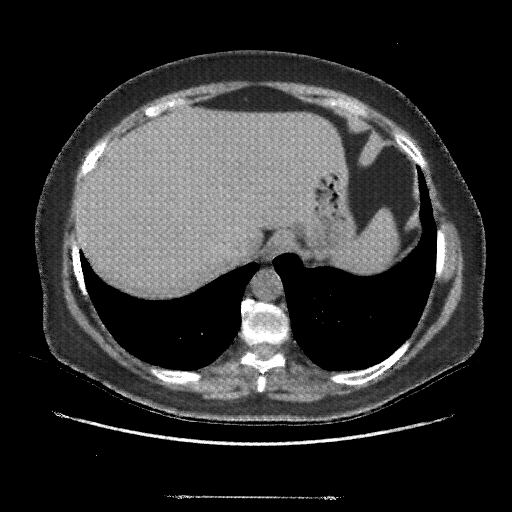

Generated VENOUS CT scan (A→B translation)

No window - Raw intensity values